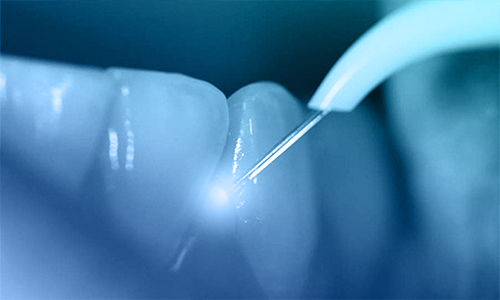

Essa non va pertanto intesa in senso di minore radicalità chirurgica, ma nel senso di ridurre le complicanze legate a vie di accesso o tecniche più traumatiche. Le nuove tecnologie usate oggi sono: Laser, Radiofrequenze, , Fibre ottiche, L, Microscopio chirurgico, Debrider o Shaver.